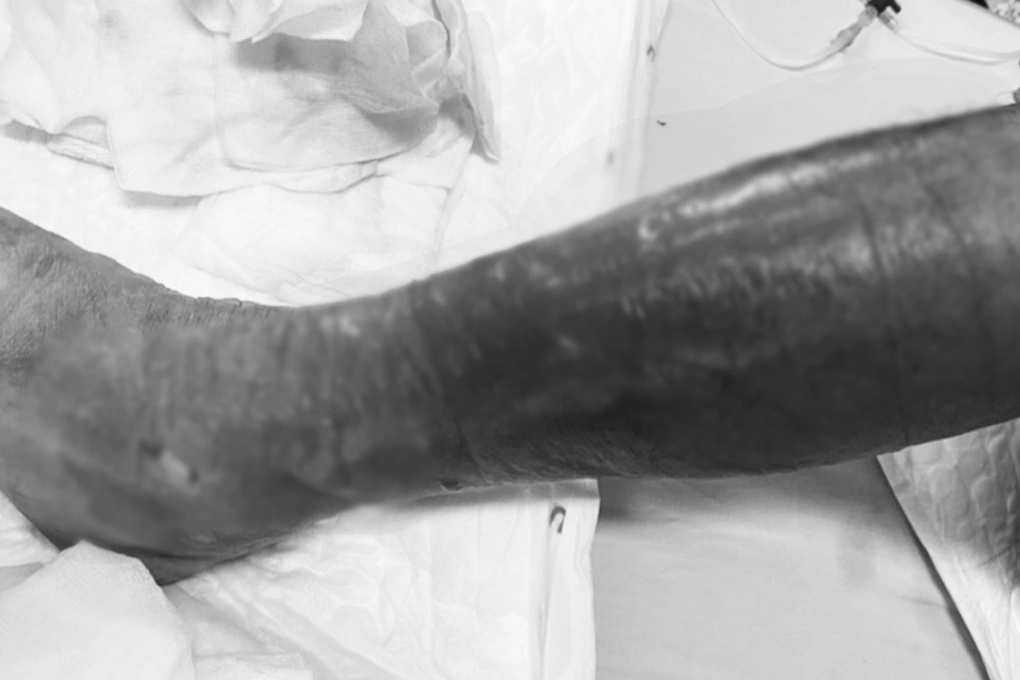

Theo lời kể của gia đình, trước khi nhập viện hai ngày, ông R. có lội bùn. Sau đó, vùng cẳng chân phải bệnh nhân đau nhức, sưng đỏ, hoại tử. Nghiêm trọng hơn, khu vực da tổn thương của ông nhanh chóng lan rộng lên tới đùi và vùng bụng dưới chỉ trong một ngày.

| Chân người đàn ông bị hoại tử nặng, một ngày sau khi lội bùn (Ảnh: BV). |